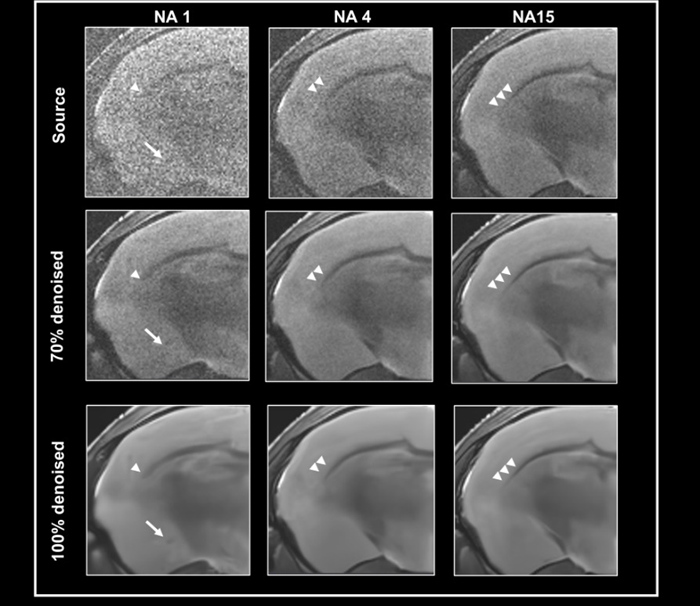

To test the efficacy of the denoising algorithm with images of varying levels of tissue contrast, ex vivo data of a fixed mouse brain was obtained with a nominal voxel size of 55 x 55 x 800 µm3 at 3 Tesla, either with no averaging, 4, or 15 averages (Fig 3).

The contrast-to-noise ratio for the corpus callosum and cortex is 2.47±0.45, 4.59±0.01, and 12.03±0.81, respectively. Images were reconstructed without 70% and 100% denoising.

Given the relatively high resolution, the image without averaging has low tissue contrast and noise, which can be reduced by utilizing averaging during acquisition or denoising during reconstruction.

Comparing denoised images taken with varying average numbers demonstrates that denoising might magnify false contrast in circumstances of low tissue contrast, i.e. no averaging (Fig 3, arrow).

Denoising images with low tissue contrast

Figure 3. Denoising images with low tissue contrast. A) Axial T2-weighted TurboRARE images of a fixed mouse head were acquired at 3 Tesla with 1, 4 and 15 number of averages (NA), respectively. Images have a nominal voxel resolution of 55 x 55 x 800 μm3. Image reconstruction was performed without (Source) and with 70 % and 100 % denoising. Each denoised image was reconstructed with a network Strong and a pre-denoising of 50 % was applied. The arrows point to a structure in the NA1 images, that is faintly visible in the image that has not been denoised and that becomes more apparent with increasing denoising. The arrowheads point to the corpus callosum which becomes more visible. Resolution of fine structure requires high tissue contrast with averaging. Image Credit: Bruker BioSpin Group

This structure, which is slightly visible in the noisy image without denoising but is difficult to differentiate from the surrounding tissue, is improved by raising the level of denoising.

A comparison of images with varying amounts of averaging shows that denoising makes the corpus callosum more visible. To resolve the fine structure of the corpus callosum's extent, strong tissue contrast and averaging are required. If this is the case, denoising improves visualization.